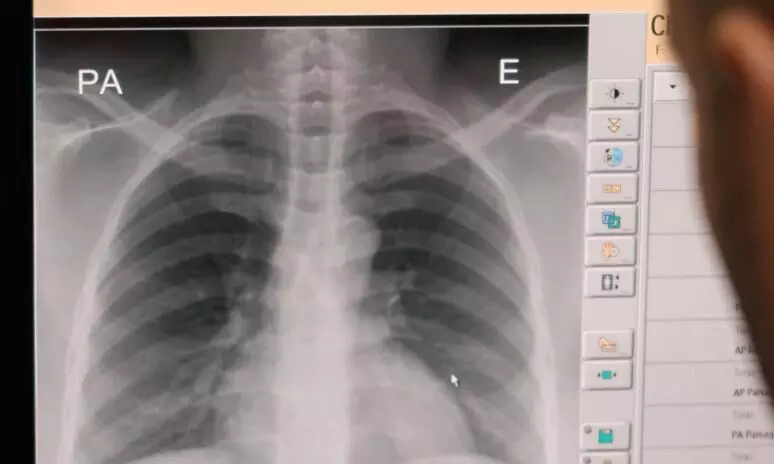

text_fieldsബംഗളൂരു: കോവിഡ് ഭേദമായവരിൽ ക്ഷയരോഗം സ്ഥിരീകരിക്കുന്ന സാഹചര്യത്തിൽ പ്രതിരോധപ്രവർത്തനങ്ങളുടെ ഭാഗമായി പ്രത്യേക പരിശോധന കാമ്പയിനുമായി ആരോഗ്യവകുപ്പ്. കോവിഡ് വന്നുപോയവരുടെ വീടുകളിൽ ആശാവർക്കർമാരും ആരോഗ്യപ്രവർത്തകരും സന്ദർശനം നടത്തി ക്ഷയരോഗ പരിശോധനക്ക് വേണ്ട തുടർ നടപടികൾ സ്വീകരിക്കും. പ്രത്യേക പരിശോധന ക്യാമ്പുകളും ഇതിനായി നടത്തും. കോവിഡും ക്ഷയവും ശ്വാസകോശത്തെ ബാധിക്കുന്നതിനാലാണ് കോവിഡ് ഭേദമായവരില് ക്ഷയം ബാധിക്കാതിരിക്കാനുള്ള മുന്കരുതല് സ്വീകരിച്ചുവരുന്നതെന്ന് ആരോഗ്യമന്ത്രി ഡോ. കെ. സുധാകര് പറഞ്ഞു. വിധാന് സൗധയില് നടന്ന ചടങ്ങില് മന്ത്രി സുധാകര് പരിശോധന യജ്ഞം ഉദ്ഘാടനം ചെയ്തു.